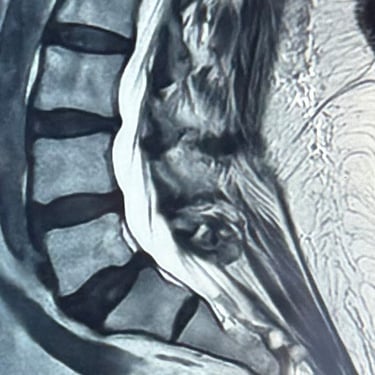

La listesis lumbar L5–S1 es una afección en la que una vértebra se desliza sobre otra, provocando inestabilidad, dolor lumbar y, en muchos casos, compresión de las raíces nerviosas. Cuando el tratamiento conservador no logra controlar los síntomas, la fusión intersomática transforaminal (TLIF) se presenta como una opción quirúrgica efectiva. Este procedimiento permite descomprimir las estructuras nerviosas, restaurar la alineación vertebral y lograr una fijación sólida mediante tornillos transpediculares e injerto óseo. La técnica TLIF reduce el dolor, mejora la estabilidad de la columna y favorece una recuperación funcional progresiva y segura.